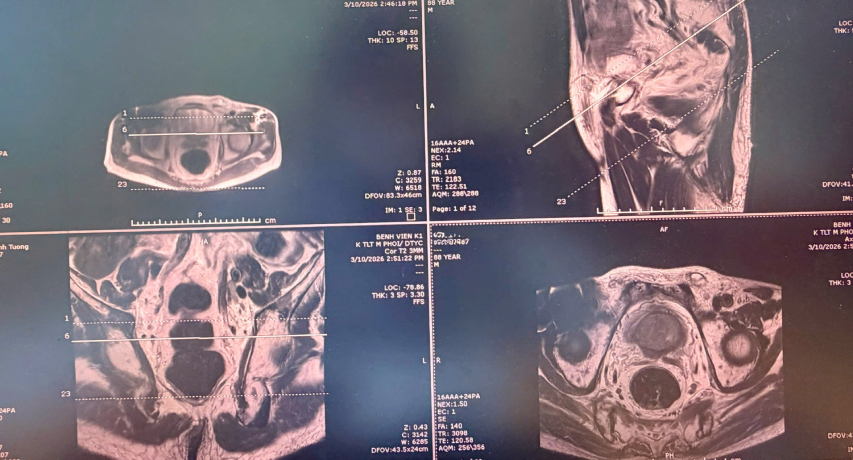

Kết quả chụp cộng hưởng từ đa tham số (mpMRI) xác định tuyến tiền liệt của ông T. có tổn thương nghi ngờ ác tính cao (PIRADS 5), kích thước khoảng 9×12mm, xâm lấn túi tinh và có dấu hiệu di căn xương. Hình ảnh học đóng vai trò quan trọng trong việc khoanh vùng tổn thương, làm cơ sở để thực hiện sinh thiết chính xác.

Dựa trên các dữ liệu này, các bác sĩ đã tiến hành sinh thiết đích qua tầng sinh môn. Kỹ thuật sinh thiết đích này được chuyển giao từ các chuyên gia hàng đầu châu Âu và được đánh giá an toàn hơn so với đường trực tràng, giảm nguy cơ nhiễm khuẩn. Đặc biệt, việc sinh thiết này phù hợp với người bệnh cao tuổi và có bệnh lý đi kèm. Nhờ kết hợp hình ảnh MRI và siêu âm đầu dò, mẫu mô được lấy đúng vị trí tổn thương, giúp nâng cao độ tin cậy của kết quả giải phẫu bệnh.